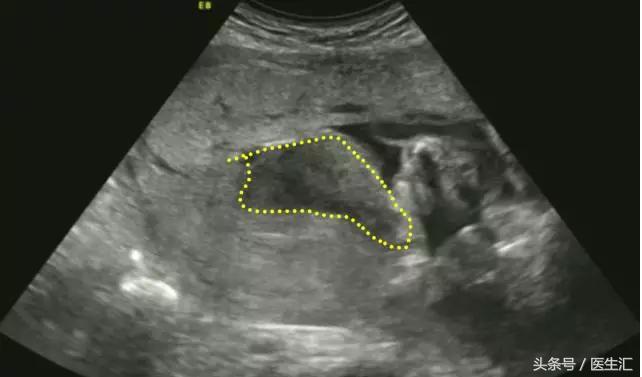

3.胎盘囊肿:位于胎盘内的羊膜面或母面,边缘清楚,圆形,内为无回声。(见图4黄色圈内)

图4,胎盘胎儿面可见一囊性包块突向羊水中,大小约30mm×15mm,边界清,内部透声好。